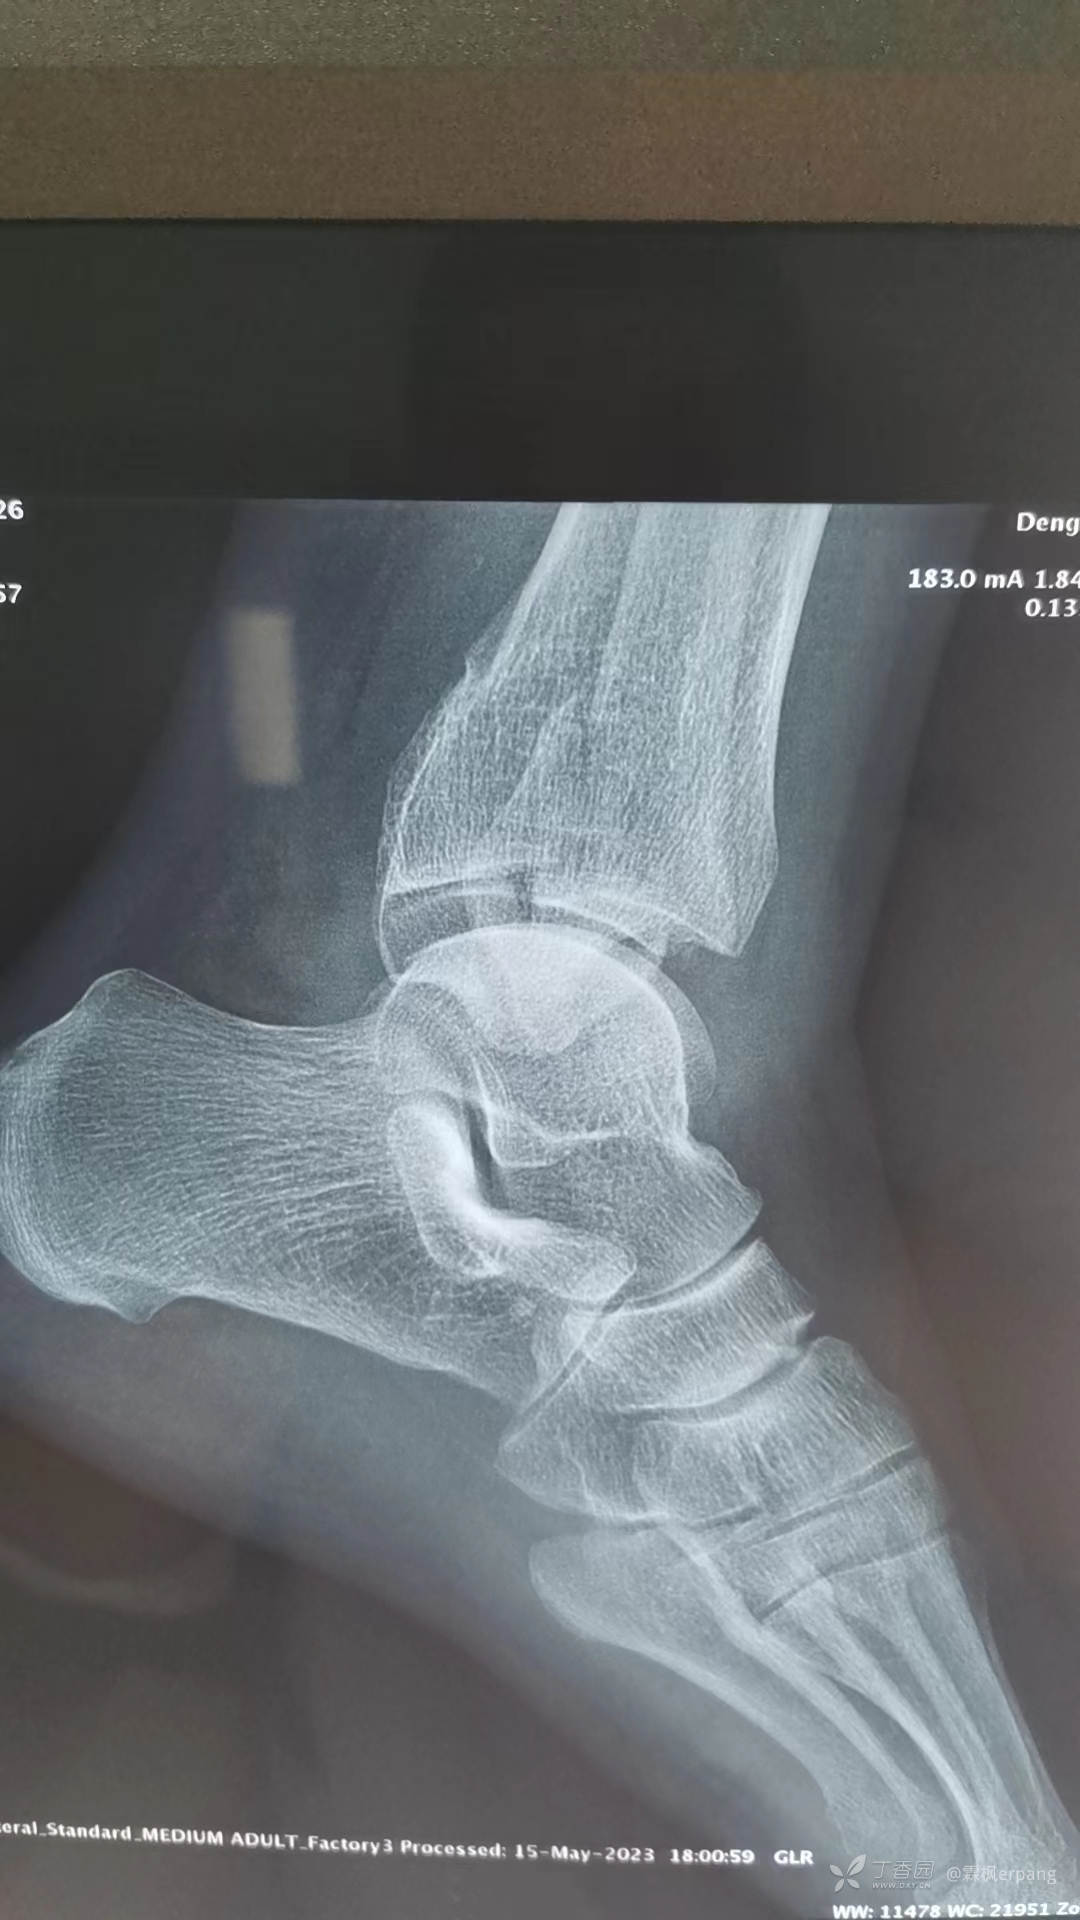

正位以为没事呢

侧位变3度了